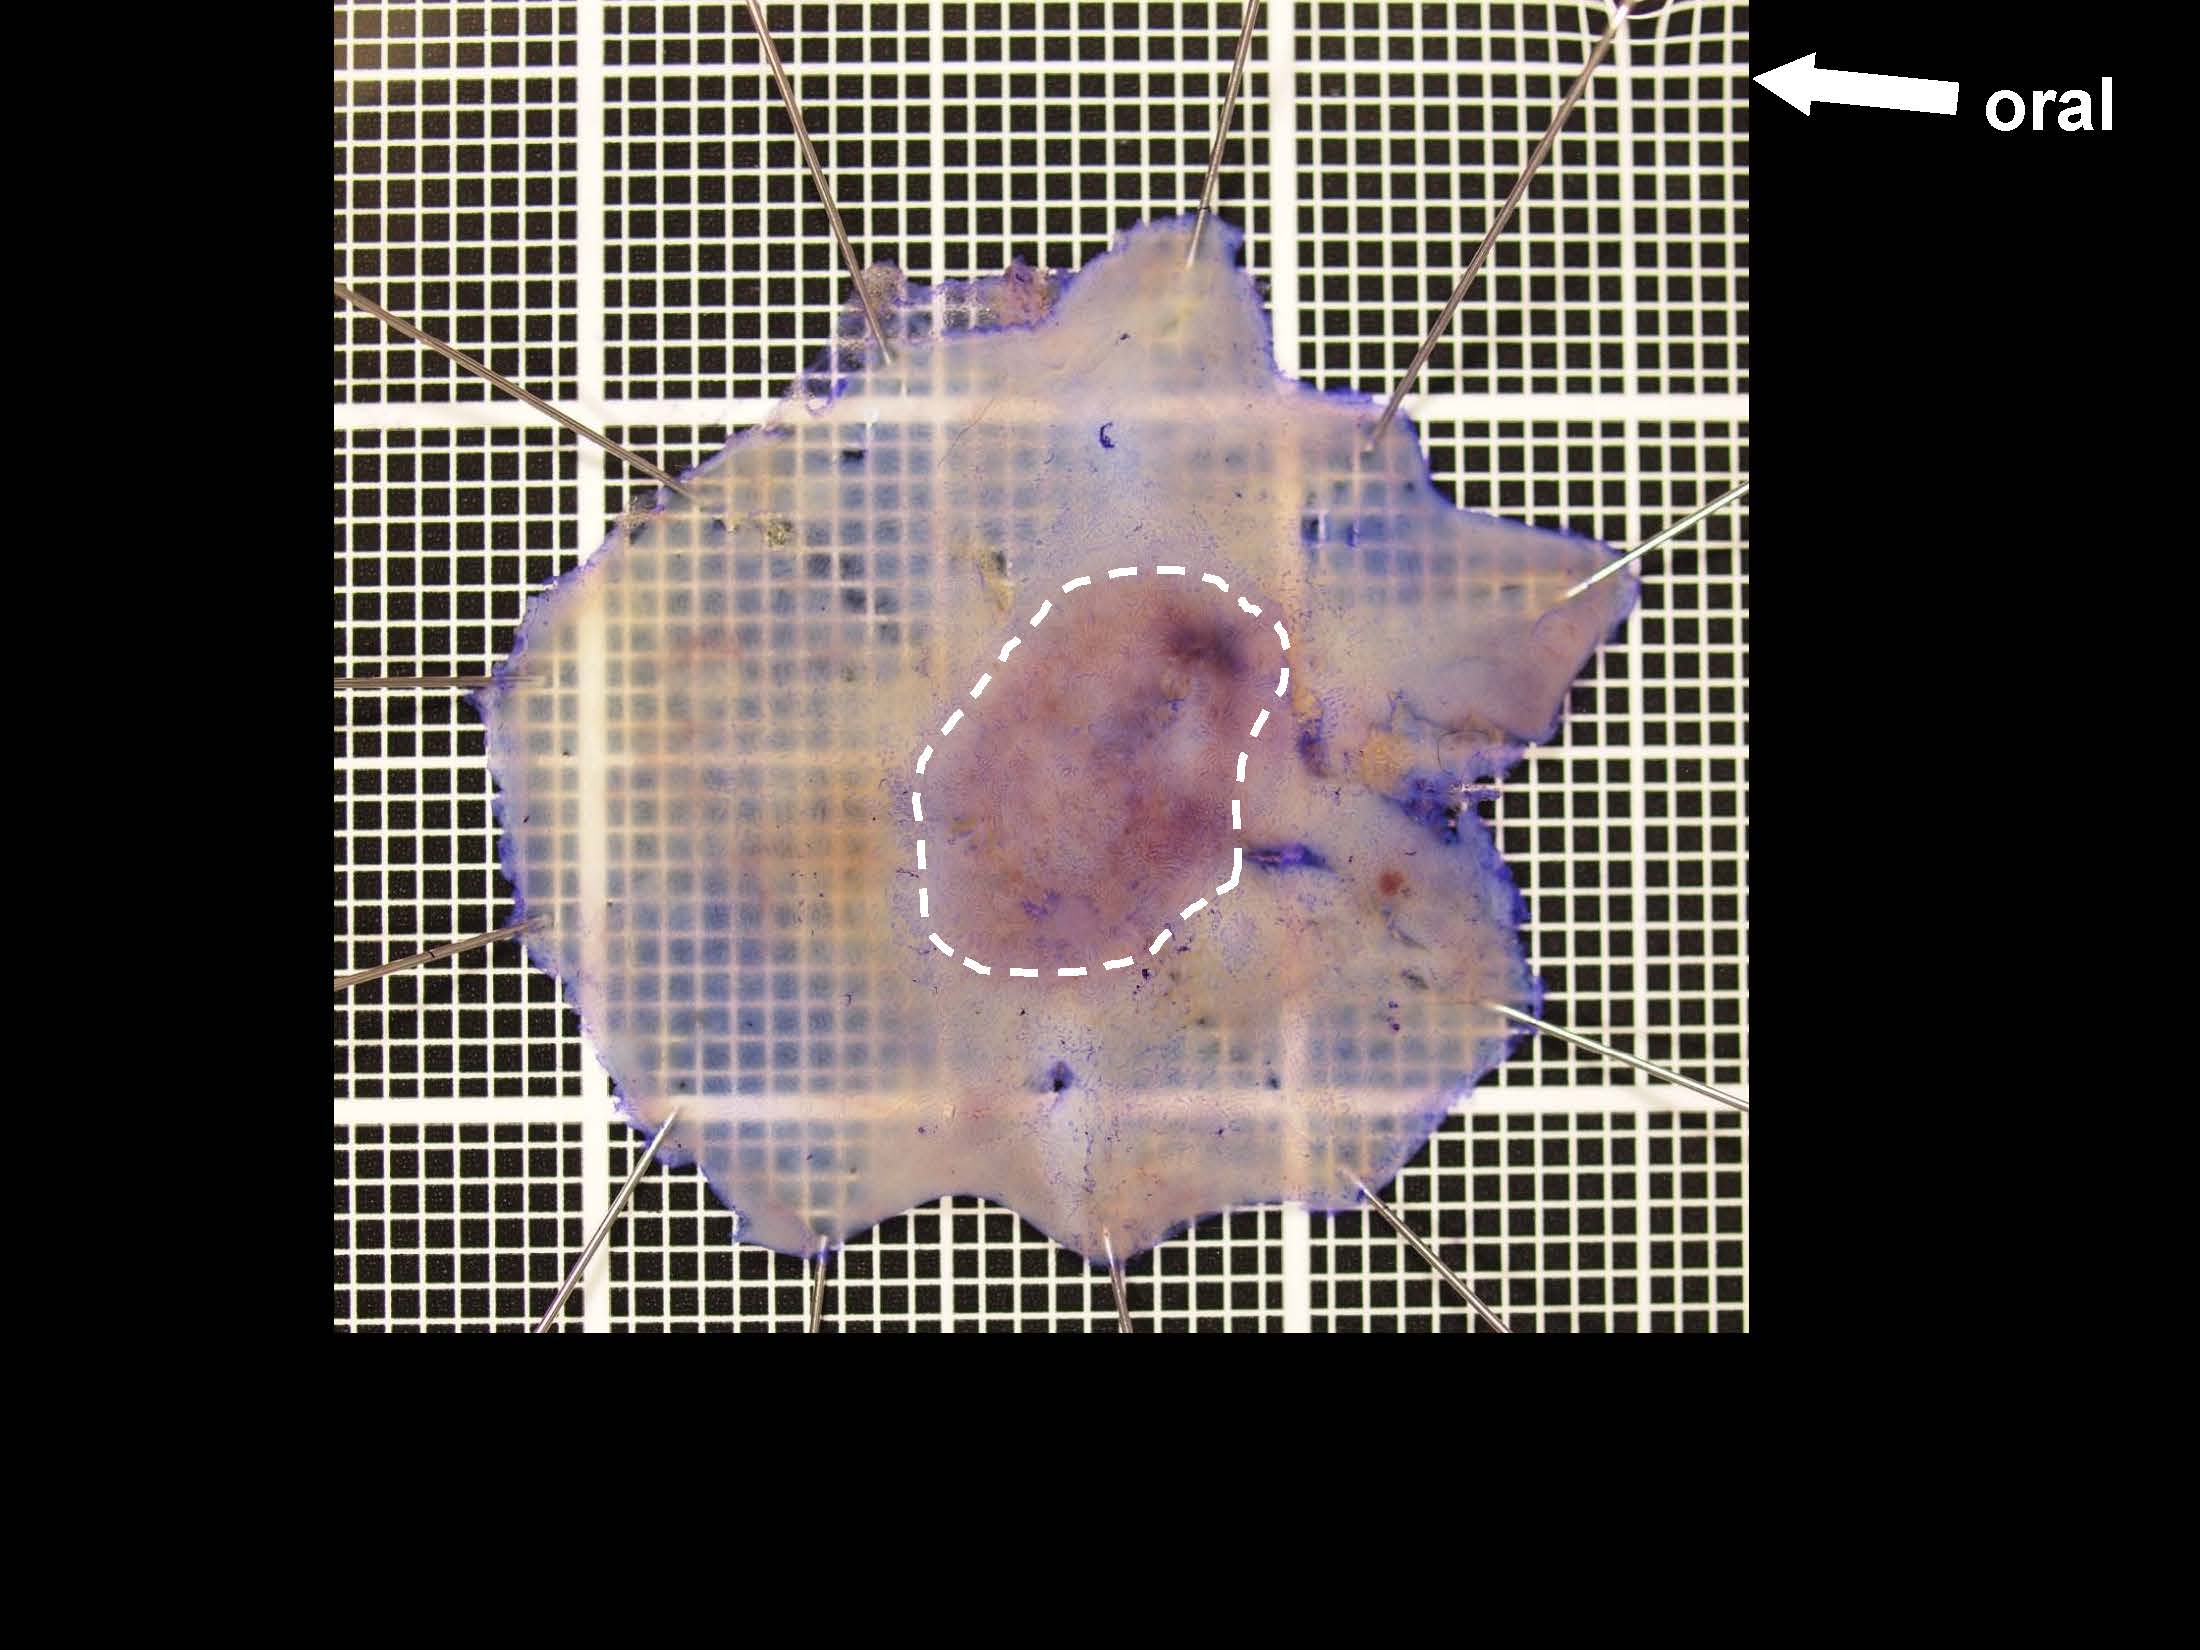

内視鏡検査・治療

消化管Mapping

消化管Mapping~大腸~

消化管Mapping~大腸~ 2021.10.27